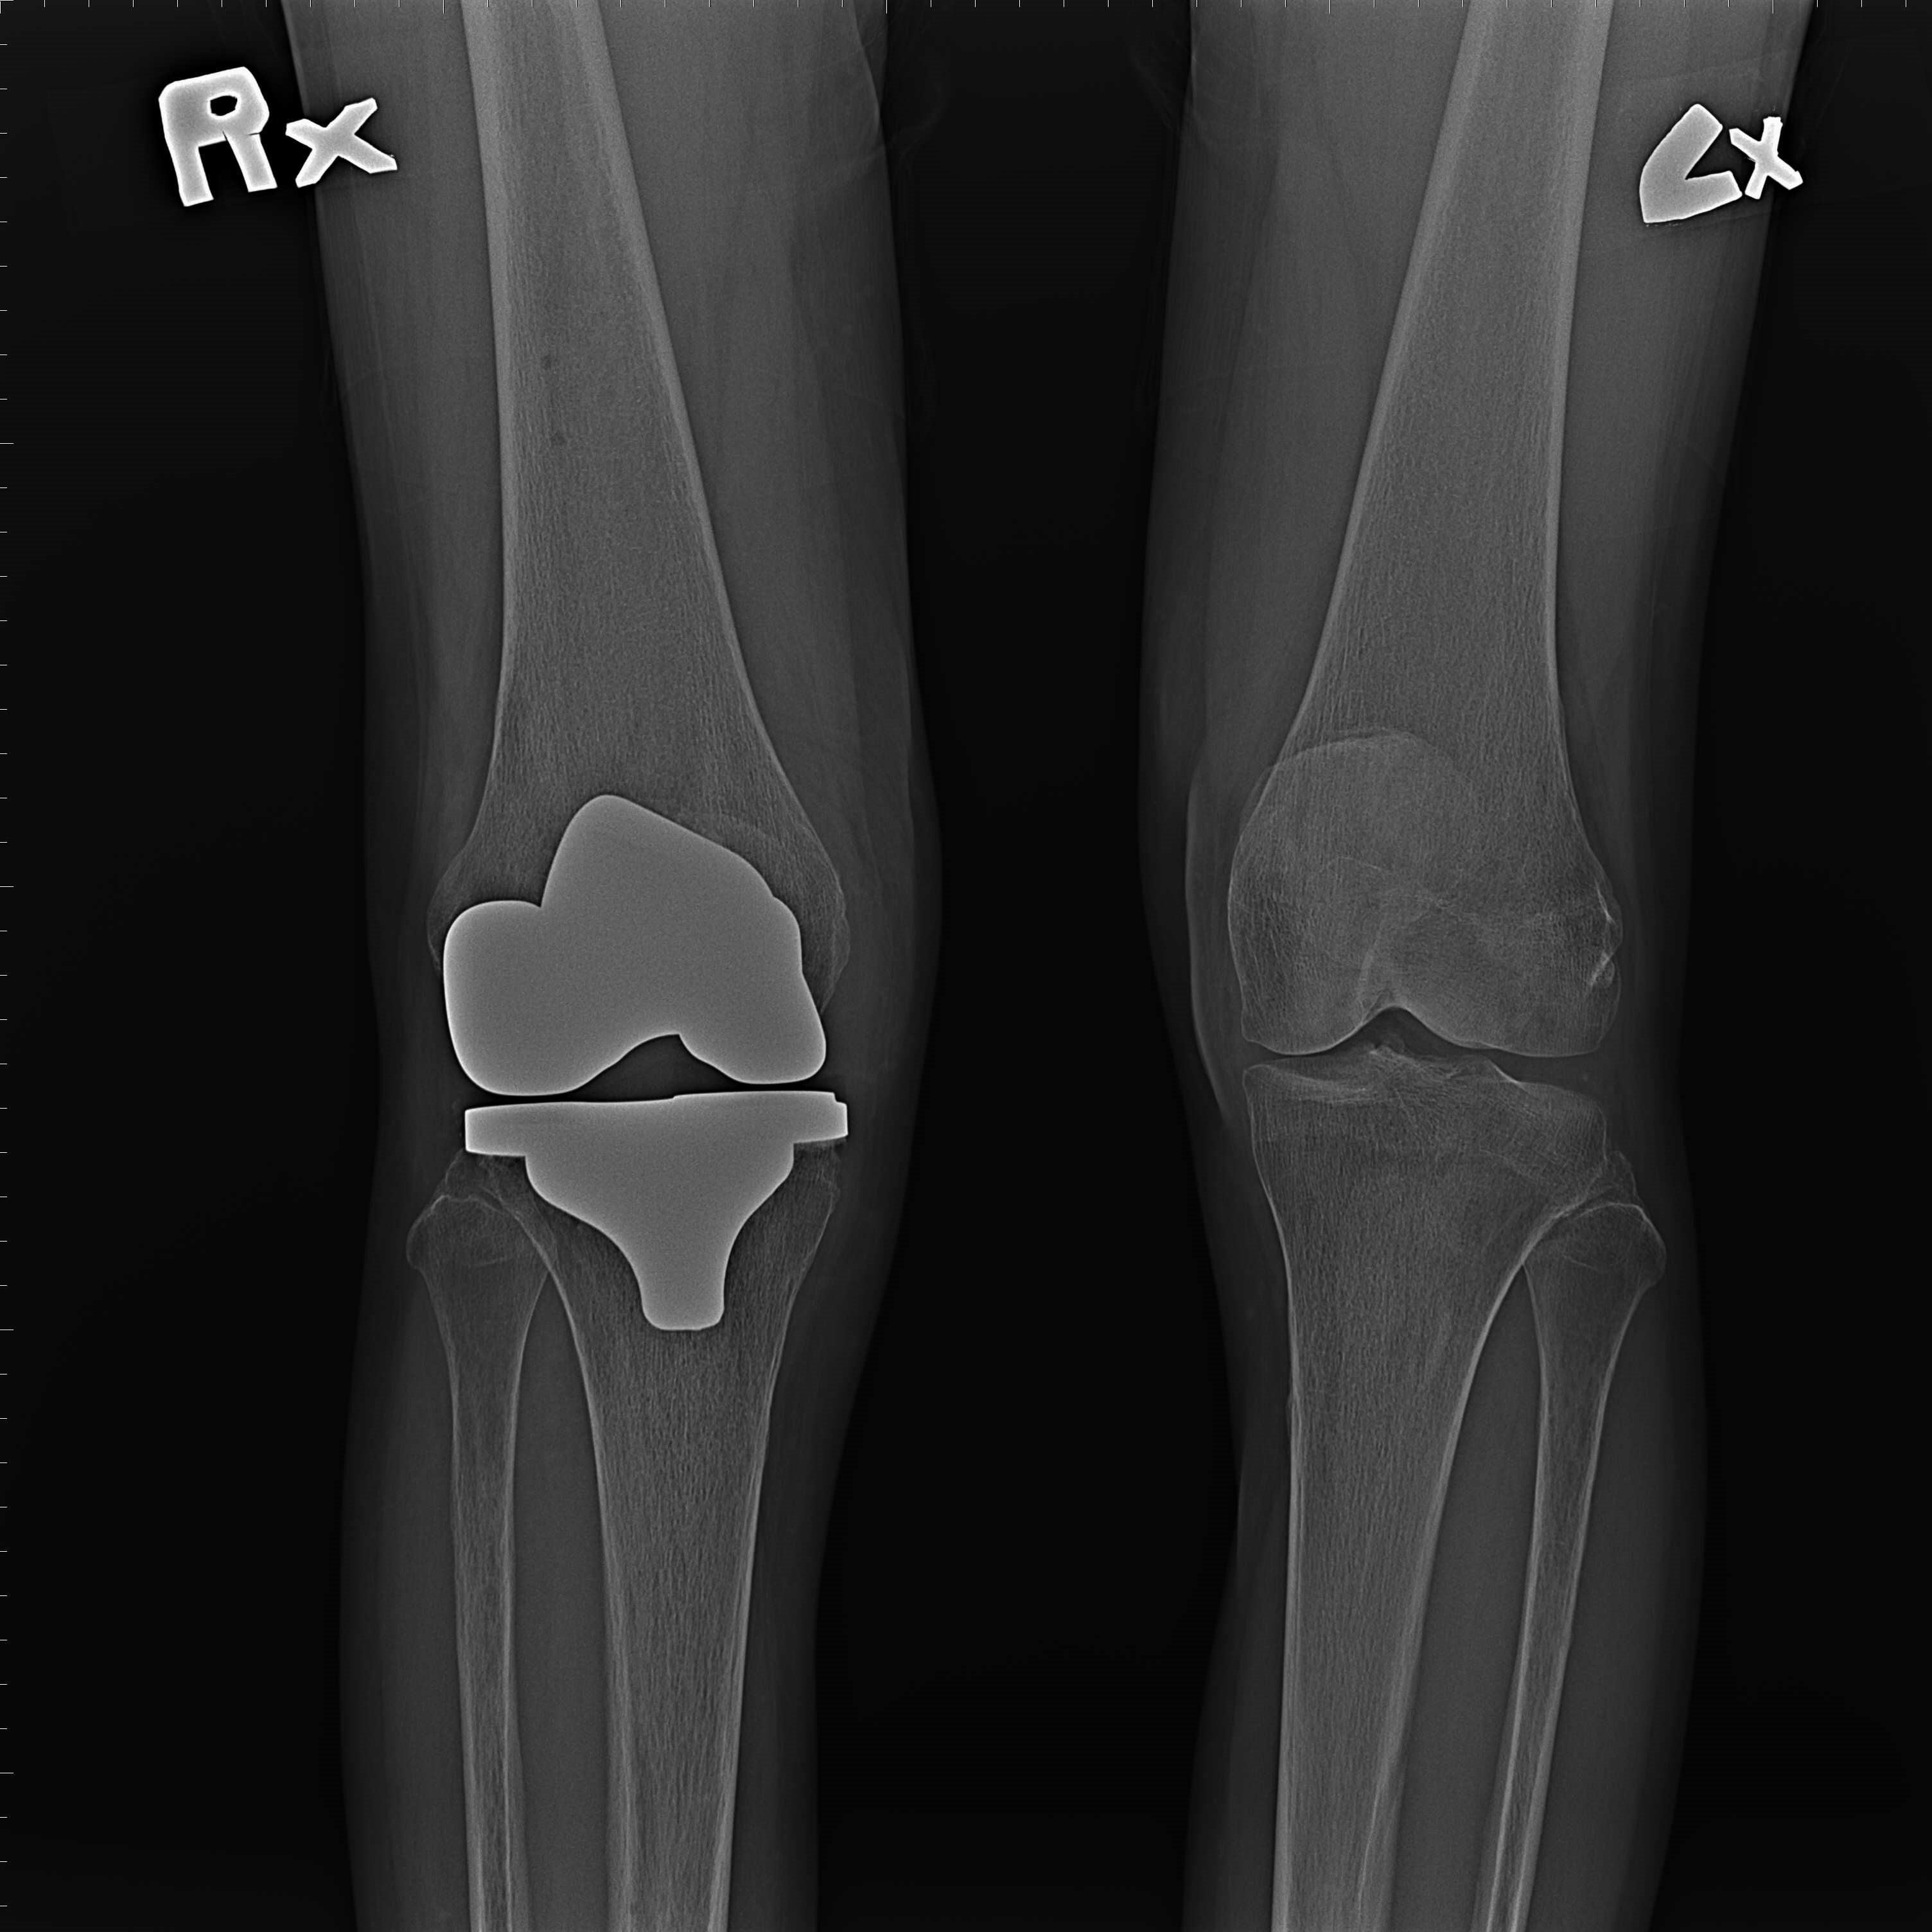

機器手臂手術 首頁 案例分享 膝關節手術 機器手臂手術 蔡女士 78歲 術前 術後 陳女士 70歲 術前 術後 術前 術後 ANGEVINE女士 73歲 術前 術後 U.S.A Mark 73歲 術前 術後 藍女士 78歲 術前 術後